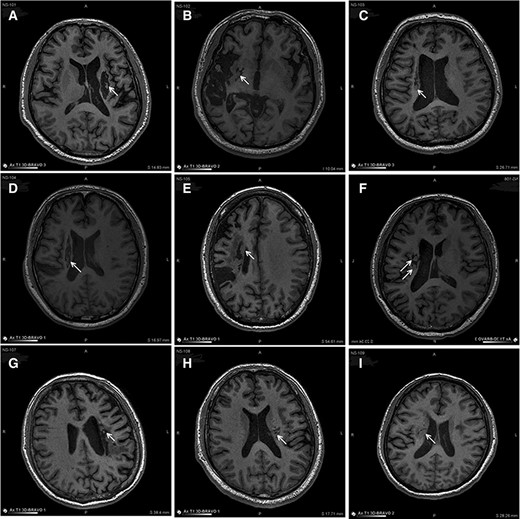

圖3:NSI-566移植后最新隨訪(fǎng)時(shí)梗塞部位的MRI。

圖中顯示的是所有9名受試者(#101–109)在NSI-566移植后最新隨訪(fǎng)時(shí)的T1MRI圖像。箭頭指示梗塞腔位置。

(A):#101,24個(gè)月時(shí),(B)#102,12個(gè)月時(shí),(C)#103,14個(gè)月時(shí),(D) #104,9個(gè)月時(shí),(E)#105,14個(gè)月時(shí),(F)#106,24個(gè)月時(shí),(G) #107,21個(gè)月時(shí),(H) #108,12個(gè)月時(shí),(I) #109,14個(gè)月時(shí)。所有九個(gè)病例中梗塞腔內均有新組織生長(cháng)。